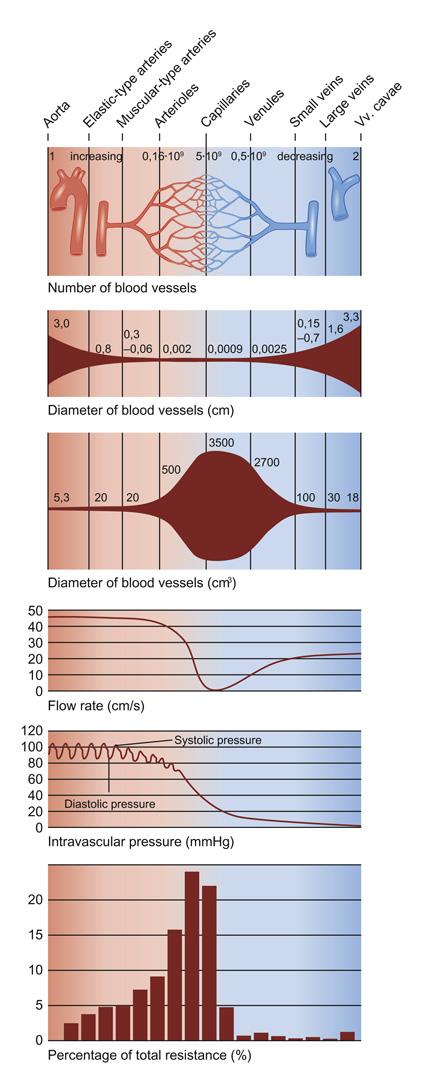

Fig 3.40: Druk, snelheid en oppervlakte bloedvaten

elastine (vooral in aorta en grote arterien) windketel effect uitwisseling t.h.v. capillairen gladde spierencellen (neemt af van aorta tot vv. cavae)